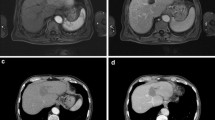

Compared to original tumour intensity, one day post-IRE DWI-b800 MRI signal intensities notably decreased in all cases (p = 0.0002), accompanied by a subsequent ADC increase (p = 0.0044). At two and 6-week follow-up, intensity remained low on DWI-b800, in comparison with the initial lesion (p = 0.0022 and p = 0.0023, respectively) and high on ADC (p = 0.0010 and p = 0.0022, respectively). One day post-IRE, small areas of diffuse hyperintensity representing blood residues were detected in all ablated areas on precontrast T1-weighted images. At this point, the ablation zone contrast enhancement in the arterial and portal venous phase had decreased in all lesions as compared to initial tumour intensity (p = 0.0099 and p = <0.0001). In the portal venous phase, a hyperintense rim surrounding the IRE ablation zone was found in 71 % (n = 16) both 1 day and 2 weeks post-IRE, and was less often identified at 6-week follow-up (29 %, n = 6). At 2- and 6-week follow-up, tumour intensity remained low for the arterial phase (p = 0.0004 and p = 0.033) and portal venous phase (p = 0.0001 and p = 0.0009). On the T2-weighted sequences, ablation zone intensity during follow-up did not significantly differ from the initial tumour intensity. However, a remarkable hypointense rim surrounding the ablation zone was observed in 52 % (n = 11) of patients 2 weeks post-IRE on T2-weighted MRI. An example of typical MRI features is shown in Fig. 2, corresponding to successfully ablated tumours.

Prior to IRE: (a) Isointense tumour on T1 sequence (b) Hypointense (-) tumour on T1 sequence (portal venous phase) (c) Hyperintense tumour on T2 sequence (d) Hyperintense (++) tumour on DWI-b800 sequence (e) Hypointense (-) tumour on ADC map. 1 day post-IRE: (f) Isointense IRE ablation zone with small hyperintense blood residues on T1 sequence (g) Hypointense (---) IRE ablation zone plus rim-enhancement surrounding the treated area on T1 sequence (portal venous phase) (h) Hyperintense (+) IRE ablation zone on T2 sequence (i) Hyperintense (+) IRE ablation zone on DWI-b800 sequence (j) Isointense IRE ablation zone on ADC map. 2 weeks post-IRE: (k) Isointense IRE ablation zone on T1 sequence (l) Hypointense (---) IRE ablation zone plus rim-enhancement surrounding the treated area on T1 sequence (portal venous phase) (m) Hyperintense (+) IRE ablation zone plus hypointense rim enhancement surrounding the treated area on T2 sequence (n) Hyperintense (+) IRE ablation zone on DWI-b800 sequence (o) Isointense IRE ablation zone on ADC map. 6 weeks post-IRE: (p) Isointense IRE ablation zone on T1 sequence (q) Hypointense (--) IRE ablation zone on T1 sequence (portal venous phase) (r) Hyperintense (+) IRE ablation zone plus hypointense rim enhancement surrounding the treated area on T2 sequence (s) Hyperintense (+) IRE ablation zone on DWI-b800 (t) Isointense IRE ablation zone on ADC map